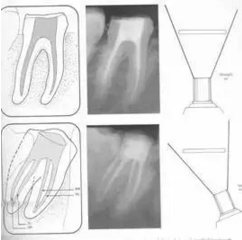

二、根管預(yù)備后形態(tài)

牙體缺損的修復(fù)需要將剩余牙體組織制備成一定形態(tài),以利修復(fù)體的良好固位。根管充填為了致密封閉根管系統(tǒng)也需要良好的根管預(yù)備后形態(tài)。

常規(guī)概念的根管預(yù)備后形態(tài)有:

( 1 )便宜形態(tài)( convenience form )

( 2 )保持形態(tài)( retention form )

( 3 )抵抗形態(tài)( resistance form )

1. 便宜形態(tài)

便宜形態(tài)是自切端或咬頜面朝向根尖的直線開擴(kuò)尖錐形態(tài),減少污染物推出根尖孔,方便沖洗、根管充填和側(cè)壁施壓。

2. 保持形態(tài)

保持形態(tài)是根尖狹窄部內(nèi) 1 — 2mm 的一段距離,由擴(kuò)大器回轉(zhuǎn)切割而不貼根管壁提拉切割制成,是擴(kuò)大器的原始形態(tài)(近似平行)。在測試主牙膠尖時給測試者有一個牽引抵抗 (tugback) 的感覺。

3. 抵抗形態(tài)

抵抗形態(tài)是根管預(yù)備的根尖形態(tài),它是由擴(kuò)大器或根管銼尖端 75 度角自然切割而成。其目的是防止根管充填材超出根尖孔,并且使根尖封閉更加嚴(yán)密。

三、開髓孔

1. 正常開髓孔的位置和大小

左圖為正常開髓孔的大小和位置。左邊圖為下顎,右邊圖為上顎。

2. 根管治療中開髓孔的設(shè)計標(biāo)準(zhǔn)

根管治療需去除髓腔內(nèi)容物(去除髓室頂),建立所有根管的入路,允許沖洗液大量沖洗。開髓孔的設(shè)計標(biāo)準(zhǔn)以建立通路為目的,從而建立良好的視野和術(shù)野。

( 1 )直線通路:根管治療時需要一個直線通路,直線通路能夠達(dá)到根尖三分之一

測量標(biāo)準(zhǔn):以允許根管器械直線并直接進(jìn)入根尖 1/3 且不接觸冠方各壁為標(biāo)準(zhǔn)。

( 2 )髓腔其他改變:如髓室頂、繼發(fā)性牙本質(zhì)、修復(fù)性或增齡性牙本質(zhì)。見左圖。

右圖中有繼發(fā)性牙本質(zhì),切削后獲得直線通路。